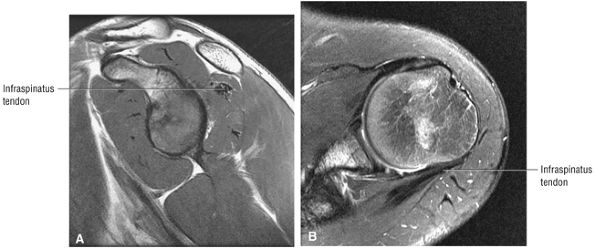

FIGURE 8.5 ● Pseudo-thickening of the infraspinatus tendon resulting from external glenohumeral joint rotation. This is not a cuff tear with retraction. (A) Sagittal PD image. (B) Axial FS PD FSE image.